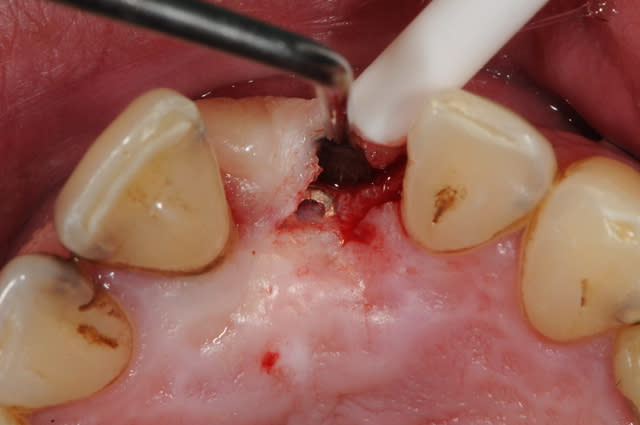

Dans le cas présenté, les images sont sur-exposées, couleur fade.

Avec un parodonte épais comme celui-ci, former la gencive n'est pas trop difficile.

With a gum biotype like this on, manipulating the gum is not very difficult.

Il y a aussi un gummy-smile et un sourire inversé, dommage après tant de couronnes.

The final result is a gummy smile with reverse smile line...too bad after all those crowns. A simple perio surgery could have give better result.